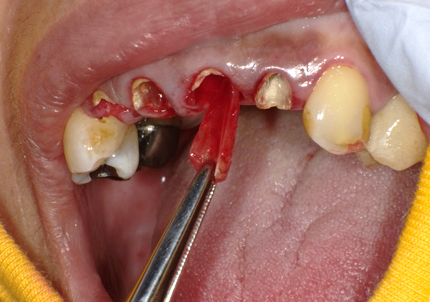

11.舌側歯牙片の抜歯

【右上1番SST 口蓋側歯根の抜歯】

【左上2番 SST 口蓋側歯根の抜歯】